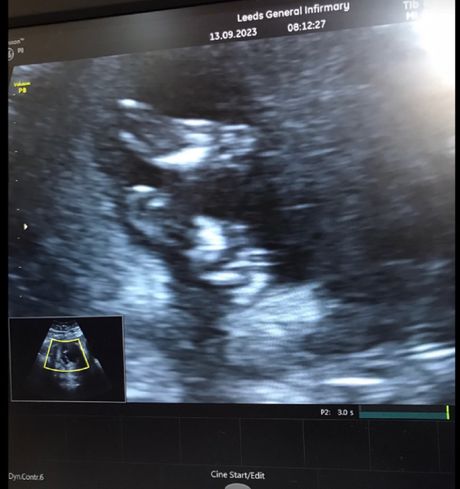

Brzi pregled je pokazao da se grlić materice otvara i da će Kelina beba biti rođena rano.

Harper-Rouz je rođena 14. septembra 2023, sa samo 18 nedelja i tri dana, u početku se sama kretala i disala - ali je umrla 30 minuta kasnije u maminom naručju. Imala je slabih 0,4 kilograma.